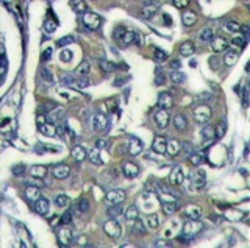

- Experimental details

- Formalin-fixed and paraffin-embedded human breast carcinoma reacted with EIF4E2 Antibody (N-term)(AP11781PU-N), which was peroxidase-conjugated to the secondary antibody, followed by DAB staining. This data demonstrates the use of this antibody for immunohistochemistry; clinical relevance has not been evaluated.